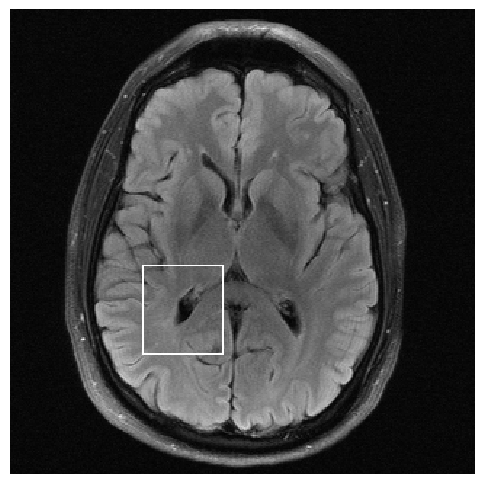

Figure 3: Examples of Reconstruction Results. Rows 1 and 3: The Ground truth (GT) fully sampled image, the reconstructed images obtained by the three models (1-3), NPB-REC, baseline, E2E-VarNet trained with Dropout, and the Std. map derived from our method for acceleration rates R=4𝑅4R=4, R=8𝑅8R=8, respectively. Rows 2 and 4: The corresponding annotated ROIS of the edema and resection cavity.

Fig. 3 presents examples of reconstruction results obtained by (1) our NPB-REC approach, (2) the baseline, and (3) Monte Carlo Dropout, for equispaced masks with two different acceleration rates R=4𝑅4R=4 and R=8𝑅8R=8. Table 1 presents the mean PSNR and SSIM metrics, calculated over the whole inference set, for the three models. our NPB-REC approach achieved significant improvements over the other methods in terms of PSNR and SSIM (Wilcoxon signed-rank test, pmuch-less-than\ll1e-4). The improvement in the reconstruction performance can be noted both quantitatively from the metrics especially for masks with acceleration rate R=8𝑅8R=8 and qualitatively via the images of annotations, where our results shows less smoothness than that obtained by Dropout.